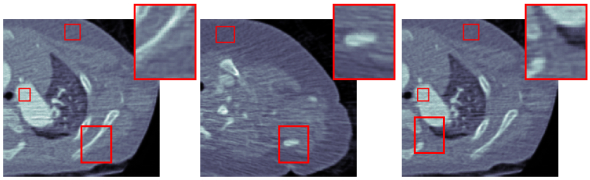

3.2 Qualitative Evaluation

We choose three representative low-dose CT images in the test dataset as shown in Fig. 3(a) for qualitative evaluation. The corresponding denoised images by CCADN, MCCAN without local cycles, MCCAN without global cycles, and MCCAN are shown in Fig. 3(b)- 3(e) respectively. Numbered areas are homogeneous regions, while areas with edges between heterogeneous regions are zoomed for visibility in Fig. 3. From the figures we can see that CCADN can successfully reduce noise in the original images. MCCAN without local cycles completely fails to produce reasonable results. A more closer examination of the images reveal that interestingly the background and the substances are approximately swapped compared with the original images. This is because the high-level features of content distribution are still kept even with such swap, and the discriminator cannot identify the generated image as “fake” because of the structure diversity in the training dataset. This aligns with our discussion on the importance of local cycles in Section 2. On the other hand, MCCAN without global cycles can successfully denoise the image and achieves similar quality compared with CCADN. This is expected as MCCAN without global cycles is essentially formed by two cascaded CCADNs. Finally, with both local and global cycles, the complete MCCAN has the smallest noise visually.

Five homogeneous areas chosen by radiologist are used for the quantitative evaluation, which are annotated by red rectangles in Fig. 3 and numbered from 1 to 5. The normalized quantitative results are shown in Table 1. CCADN can reduce the standard deviation in the five areas by 15%, 21%, 21%, 22% , and 22% respectively, with resulting mean values close to those of the original images. Although MCCAN without local cycles achieves smallest standard deviation in Areas 1, 3 and 4, it leads to meaningless output with large mean deviation from the original images, which corresponds to the structure loss in Fig. 3(c). MCCAN without global cycles has similar performance compared with CCADN. with mean values close to original and standard deviation reduction by 22%, 23%, 20%, 27%, and 19% respectively. Finally, the complete MCCAN behaves the best among all the methods: Within reasonable mean range, the standard deviations are decreased the most by 24%, 32%, 29%, 29%, and 32% from the original CT images respectively.